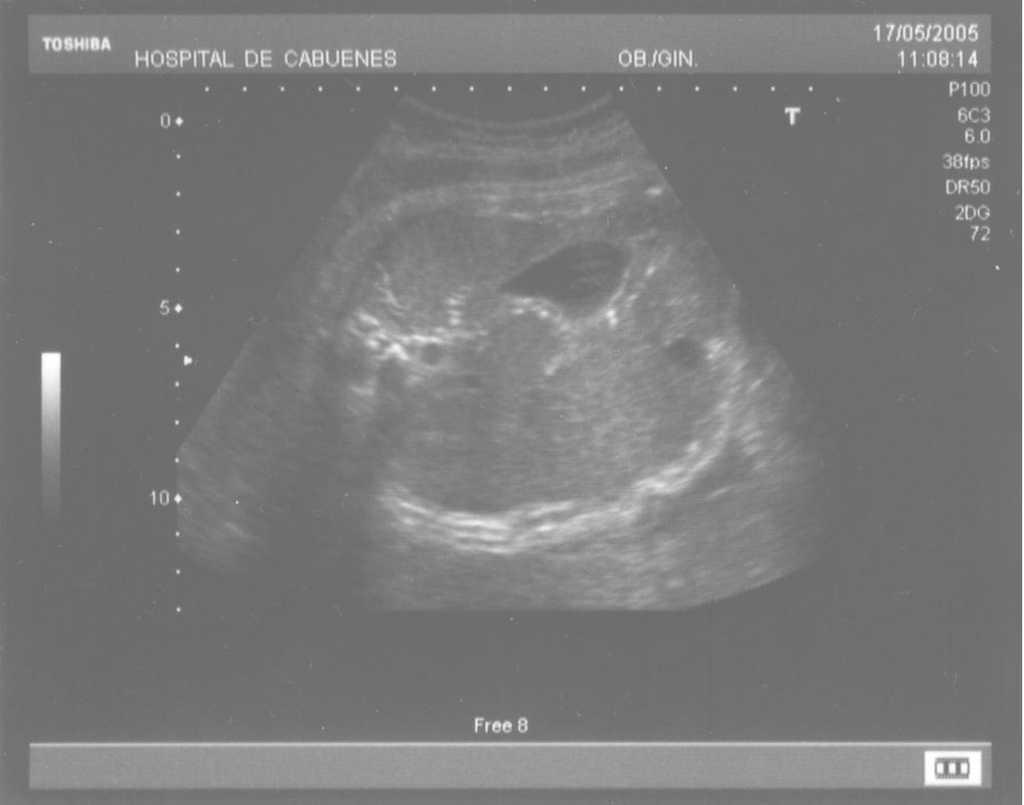

Las calcificaciones peritoneales son el hallazgo más consistente de PM y de hecho es la referencia en todas las series para establecer el diagnóstico posnatal en la radiografía simple de abdomen. Sin embargo, los criterios diagnósticos prenatales de PM no son uniformes y no se aplican de la misma manera por todos los autores. Las calcificaciones aparecen entre el 0-100% de los casos y en nuestra revisión, excluida la serie de Eckoldt et al8, en el 71,8%. Chan et al13 exigen como criterios para diagnóstico de PM la presencia de ascitis más dilatación de asas intestinales o calcificaciones. Sólo encuentran calcificaciones en 1/7 casos y argumentan que pueden pasar inadvertidas a los ultrasonidos. Eckoldt et al8, en una serie de 11 casos, no describen calcificaciones en ninguno y añaden: «no es común en nuestra institución practicar rayos X a la mujer gestante», e incluyen como diagnóstico prenatal de PM un caso con sólo ascitis, dos con ascitis e intestino ecogénico y dos con ascitis y polihidramnios, criterios que parecen insuficientes para establecer el diagnóstico de PM, aunque sea confirmado posnatalmente. Kamata et al23 sólo encuentran calcificaciones en 5/20 casos. Otros casos aislados comunicados tampoco encuentran calcificaciones1,10. El estudio de Dirkes et al14, citado en todas las comunicaciones por su clasificación de la PM en función del probable pronóstico neonatal, comunica calcificaciones en 9/9 casos y manifiestan: «el más frecuente y consistente hallazgo ecográfico, que es virtualmente patognomónico de PM, es la presencia de calcificaciones intraabdominales descartando su origen biliar, vascular, intraluminal, de órgano sólido o calcificación tumoral (...) la ascitis fetal aislada, la dilatación intestinal o el polihidramnios no son suficientes para el diagnóstico de PM». Chalubiski et al5 encuentran calcificaciones en algún momento del seguimiento prenatal en 8/9 casos y lo consideran el hallazgo más frecuente; Shyu et al12, en 16/17 casos; Tseng et al24, en 15/19 casos, y Foster et al4, en 6/7 casos y revisan los 19 casos comunicados previamente de diagnóstico prenatal de PM y encuentran calcificaciones o masas ecogénicas en 16/19 casos. Estroff et al6 comunican calcificaciones en 3/3 casos; éstas también están presentes en numerosos casos aislados1,3,7,25-27. Conviene tener presente que las calcificaciones abdominales encontradas en la PM son de localización peritoneal (extendidas por la superficie peritoneal) y deben distinguirse de las calcificaciones parenquimatosas, limitadas al parénquima hepático y, menos frecuentemente, al esplénico28. Aunque las calcificaciones peritoneales suelen ser más difusas, más numerosas y más groseras (como el caso que describimos; fig. 1) no debe obviarse este diagnóstico diferencial, de mayor importancia cuando la calcificación es el único hallazgo y de mayor dificultad cuando son escasas o se asocian con polihidramnios, pues en estas ocasiones no debemos pasar por alto la posibilidad de infección fetal u otras etiologías29. Además, debido al gran tamaño del hígado fetal, en ocasiones puede ser difícil localizar con precisión si las calcificaciones son peritoneales o hepáticas30. Sugieren una localización peritoneal: a) las calcificaciones que respetan el parénquima hepático y esplénico y se localizan en sus márgenes; b) la formación de láminas que «perfilan» el diafragma, y c) la localización en el escroto de un feto varón, que son particularmente diagnósticas de PM, debido a la conexión del saco escrotal con la cavidad peritoneal a través del proceso vaginal. Estos hallazgos estuvieron presentes en el caso que describimos (figs. 2, 3 y 4). Más raramente se localizan en el tórax por comunicación a través de los hiatos de la cava, la aorta o el esófago31. Debe tenerse presente la localización escrotal para establecer el seguimiento, pues no es inusual que en los primeros meses neonatales den lugar a masas o un escroto agudo que requieren intervención quirúrgica; la dificultad para orientar el diagnóstico es mayor cuando falta el antecedente de PM prenatal32-38.

Figura 2. Calcificaciones que respetan el parénquima hepático y esplénico.